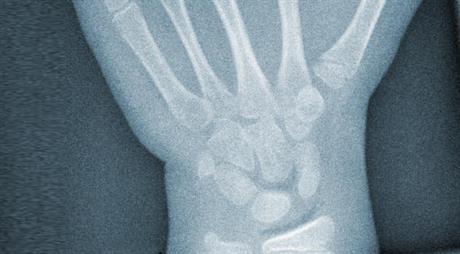

Napuknuće patele

Fraktura patele ("čašice") koljena ozbiljna je ozljeda i njenom liječenju treba pristupiti tako. Ukoliko nema pomaka koštanih ulomaka (na djelu je "napuknuće") tada je imobilizacija najbolje rješenje